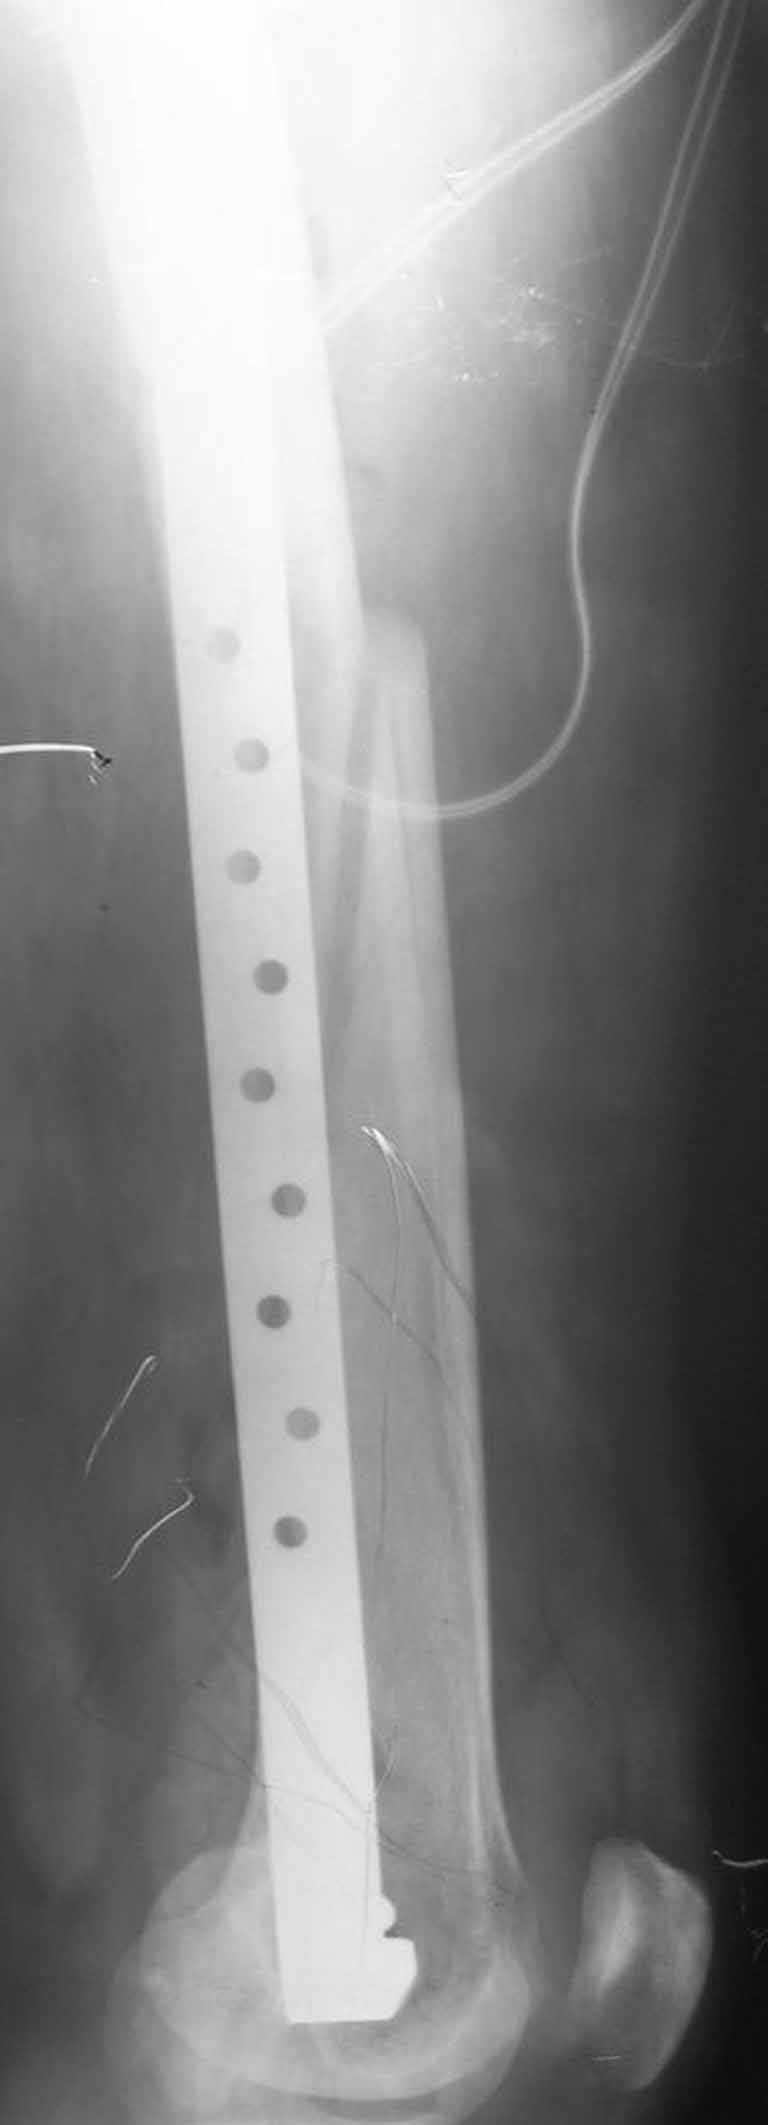

Представляю вам один из наших недавних случаев выполнения малоинвазивного остеосинтеза бедренной кости обычной пластиной 95 градусов.  Длина восстановлена с помощью дистрактора (по сути это основная и б(о)льшая часть репозиции). Произведено два небольших доступа, проведена спица направитель. Рентген-контроль для подтверждения достаточной длины/оси(ЭОП использовался в другой операционной). Создание тунеля обратной стороной фиксатора. Поворот фиксатора, введение клинка по спице. Фиксация проксимального и дистального концов пластины.

Вложение не в текстовом формате было извлечено…

Имя     : 3op1.jpg

Тип     : image/jpg

Размер  : 45470 байтов

Описание: отсутствует

Url     : http://weborto.net:8080/pipermail/ortho/attachments/20110902/aa3367e1/attachment-0009.jpg